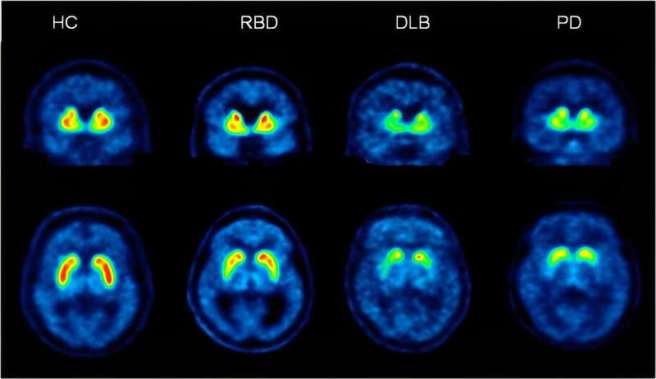

2. Longitudinal study of REM Sleep Behavior Disorder:

More research results on REM sleep behaviour disorder: The International REM Sleep Behavior Disorder Study Group presented follow-up data from 28 centers of 1160 participants followed for more than 3 years; The “findings provide optimized clinical endpoints & sample size estimates to inform future neuroprotective trials” (Click here to read more about this).